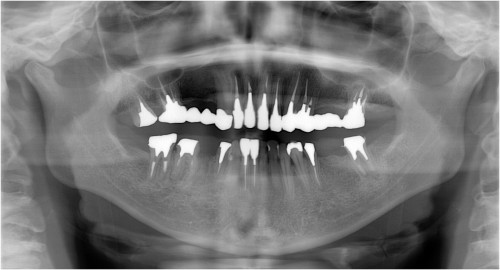

術 前 術 後

川口の歯科 歯医者 さかえ歯科クリニック

2014年12月16日